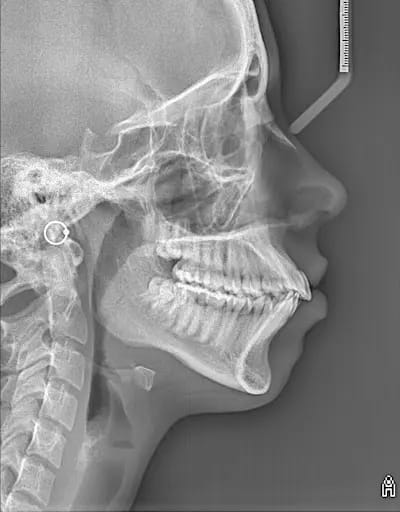

En Estudio Rx, ofrecemos el servicio de Radiografía Lateral de Cráneo, un estudio radiológico esencial en la evaluación de la estructura ósea y las relaciones anatómicas del cráneo y la mandíbula. Esta radiografía proporciona una imagen lateral del cráneo, permitiendo a los especialistas analizar con precisión las proporciones y alineaciones de los huesos faciales y dentales.

La Radiografía Lateral de Cráneo es fundamental en el diagnóstico y planificación de tratamientos de ortodoncia, cirugía maxilofacial, y en el seguimiento de problemas de crecimiento y desarrollo craneofacial. Esta técnica permite evaluar la posición de los dientes, la relación entre el maxilar y la mandíbula, y la estructura ósea del cráneo, proporcionando una visión completa que facilita un diagnóstico preciso y un tratamiento personalizado.